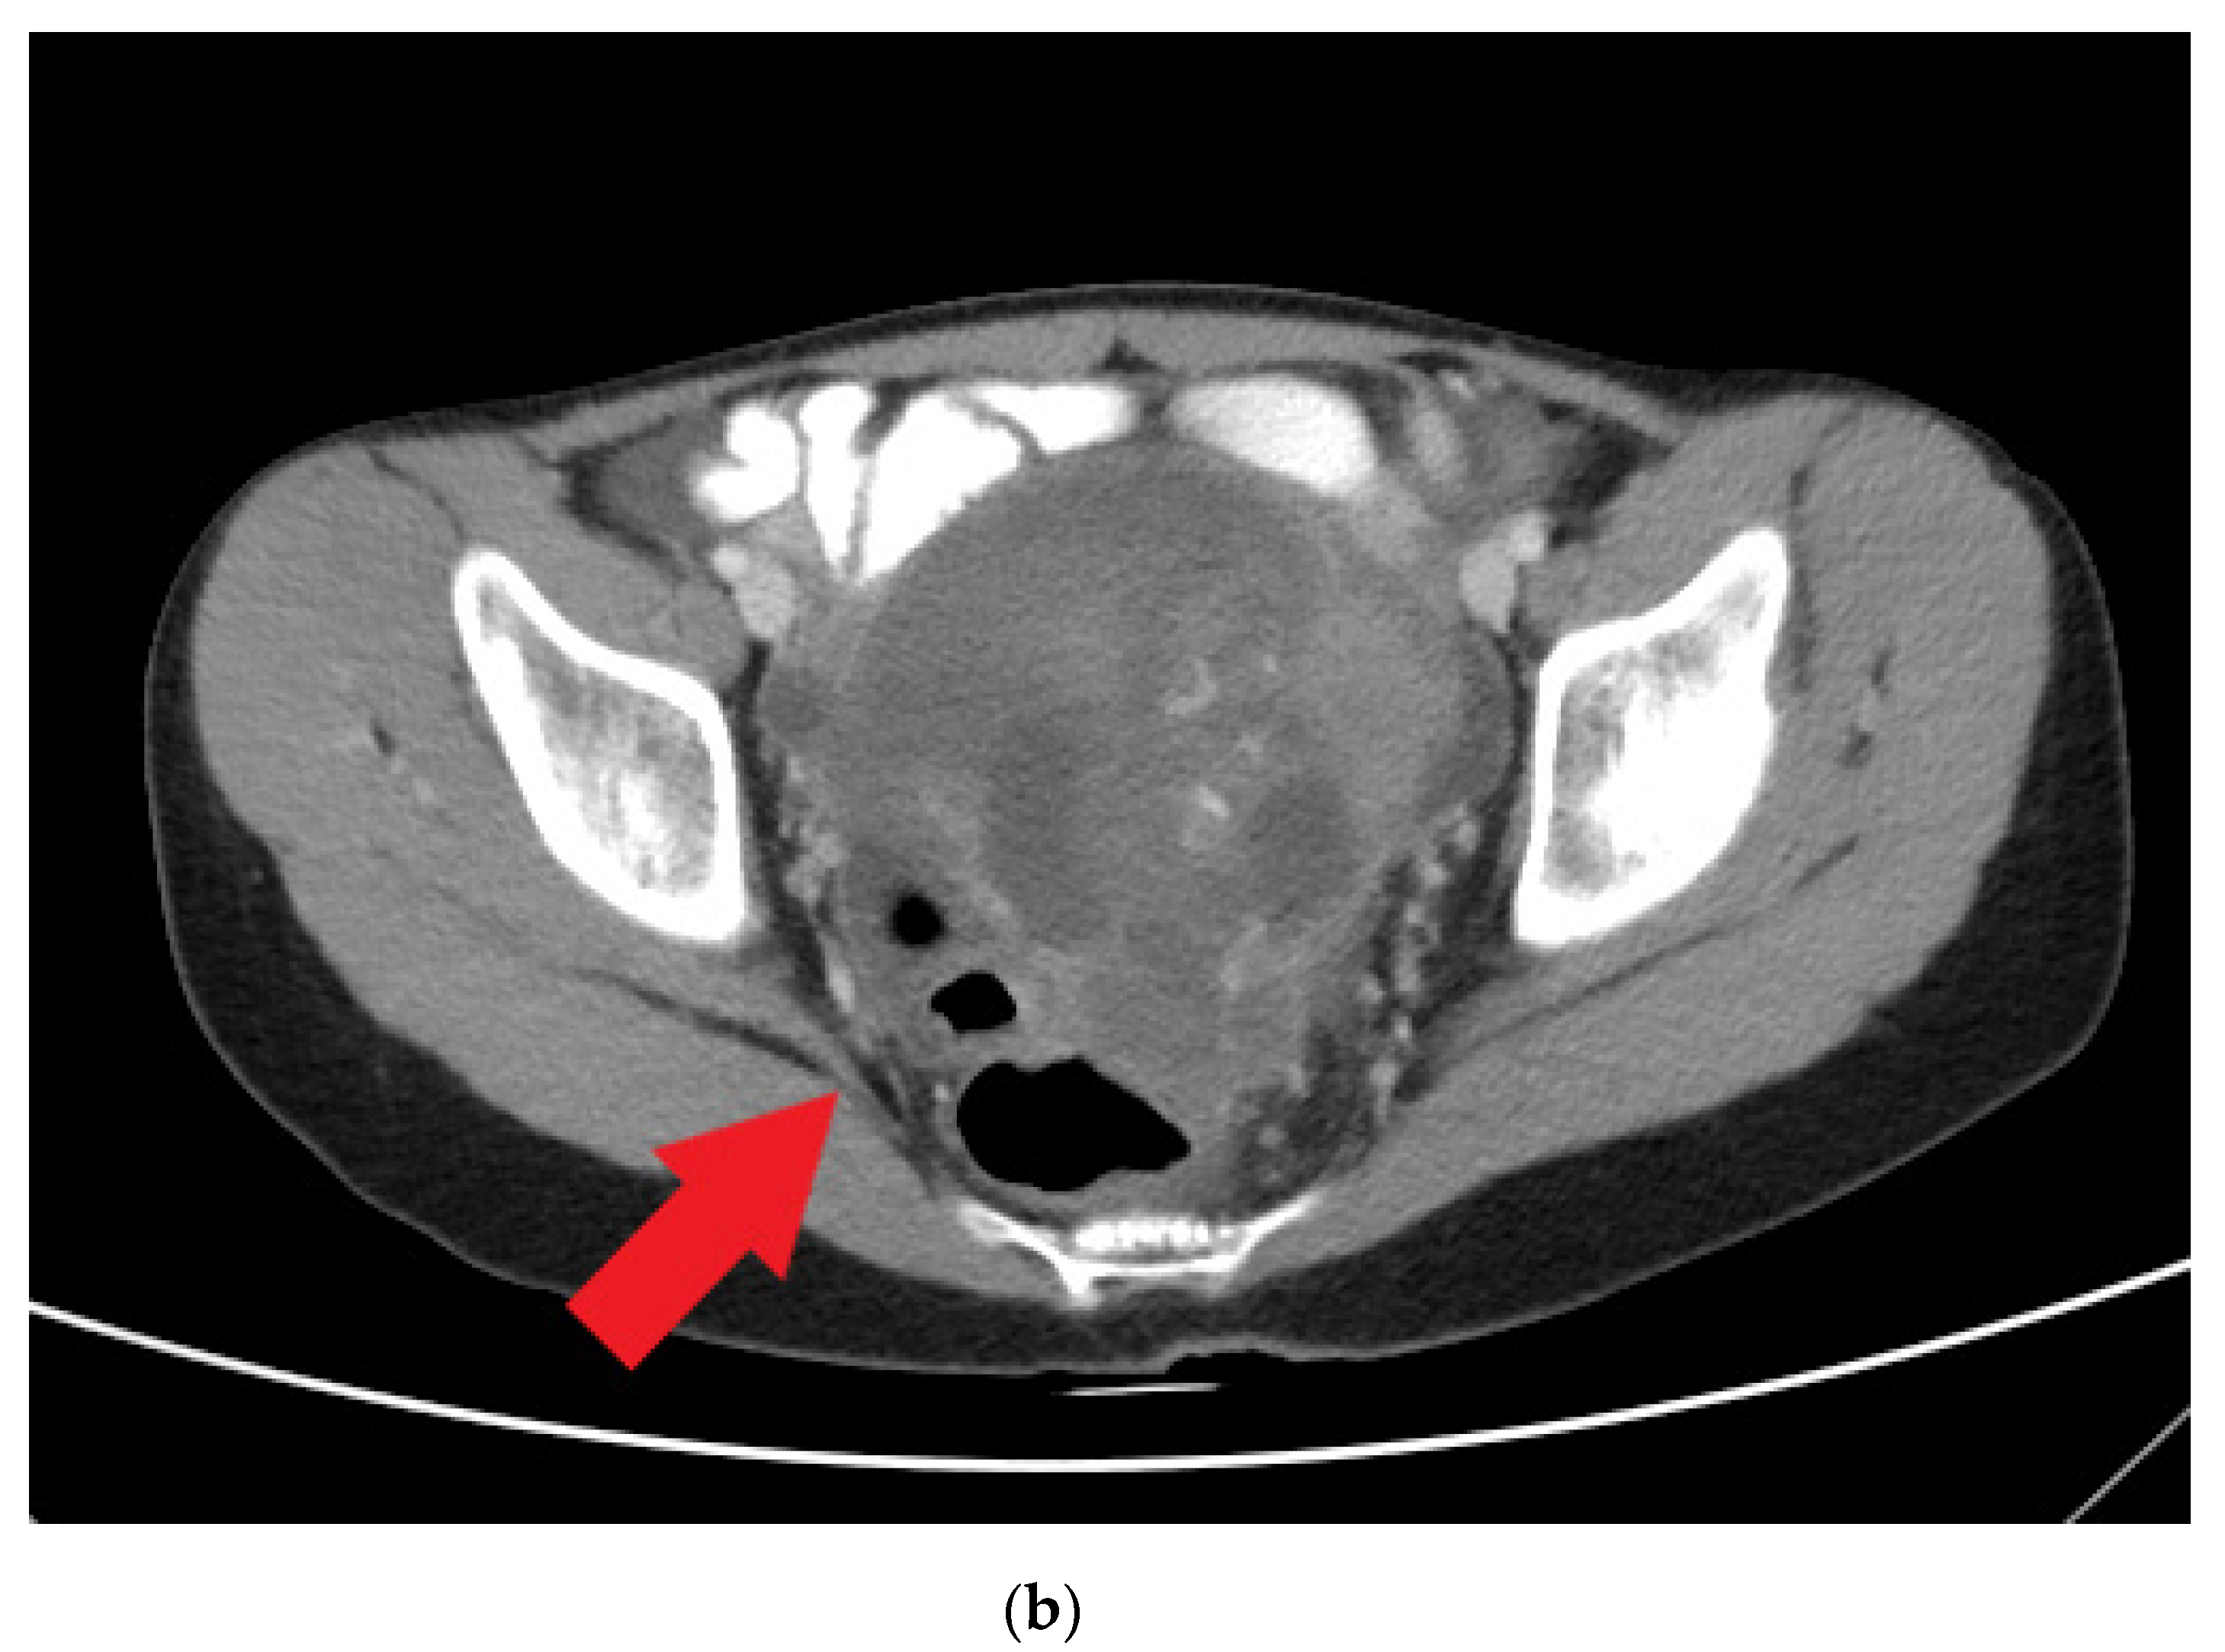

| 14 years old | Prolonged menstrual period of up to 1 month | CA-125, 77.96 unit/mL; CA-199, 57.01 unit/mL; alpha fetal protein, 94.88 ng/mL Serum albumin: 2.2 g/dL, cholesterol: 183 mg/dL, triglyceride: 133 mg/dL | CT scan: a lobulated mass lesion, maximum diameter: 10.1 cm | Malignant mixed germ cell tumor: 75% dysgerminoma, 10% immature teratoma, 10% embryonal carcinoma, and 5% yolk sac tumor | cytoreductive left salpingo-oophorectomy |